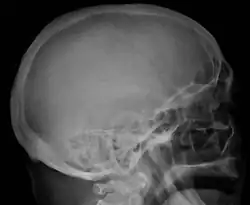

Skull X-ray showing multiple lucencies due to multiple myeloma -

Bone pain affects almost 70% of people with multiple myeloma and is one of the most common symptoms.[2]: 653 [23] Myeloma bone pain usually involves the spine and ribs and worsens with activity. Persistent, localized pain may indicate a pathological bone fracture. Involvement of the vertebrae may lead to spinal cord compression or kyphosis. Myeloma bone disease is due to the overexpression of receptor activator for nuclear factor κ B ligand (RANKL) by bone marrow stroma. RANKL activates osteoclasts, which resorb bone. The resultant bone lesions are lytic (cause breakdown) in nature. They are best seen in plain radiographs, which may show "punched-out" resorptive lesions (including the "raindrop" appearance of the skull on radiography). The breakdown of bone also leads to the release of calcium ions into the blood, leading to hypercalcemia and its associated symptoms.[24]

The diagnostic examination of a person with suspected multiple myeloma typically includes a skeletal survey. This is a series of X-rays of the skull, axial skeleton, and proximal long bones. Myeloma activity sometimes appears as "lytic lesions" (with local disappearance of normal bone due to resorption) or as "punched-out lesions" on the skull X-ray ("raindrop skull"). Lesions may also be sclerotic, which is seen as radiodense.[76] Overall, the radiodensity of myeloma is between −30 and 120 Hounsfield units (HU).[77] Magnetic resonance imaging is more sensitive than simple X-rays in the detection of lytic lesions. An MRI may supersede a skeletal survey, especially when vertebral disease is suspected. Occasionally, a CT scan is performed to measure the size of soft-tissue plasmacytomas. Nuclear Medicine Bone scans are typically not of any additional value in the workup of people with myeloma (no new bone formation; lytic lesions not well visualized on nuclear bone scan).